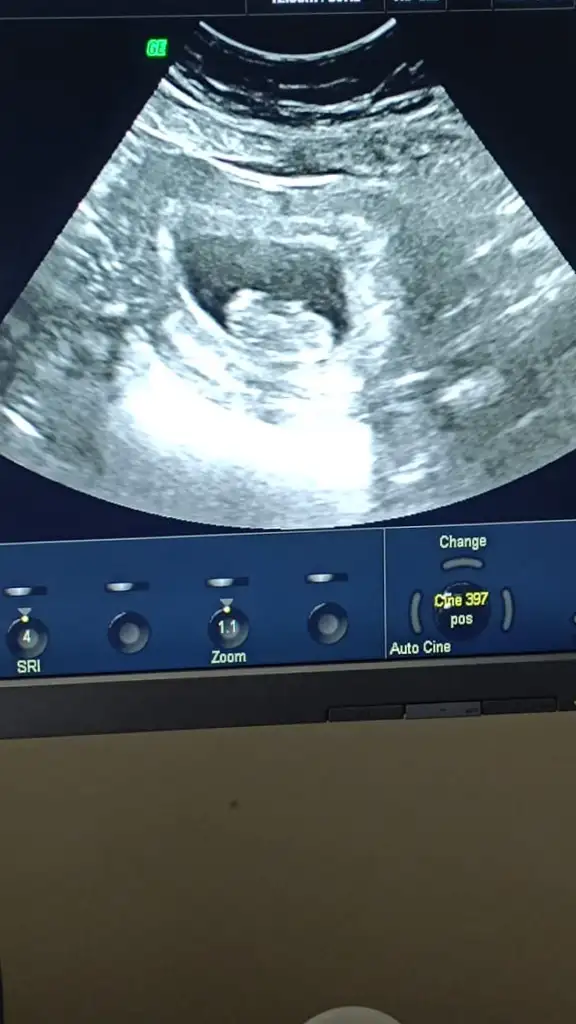

9 haftalık gebelik cinsiyet tahmini yapabilir misiniz kızlar bugün 11 haftalık 💕